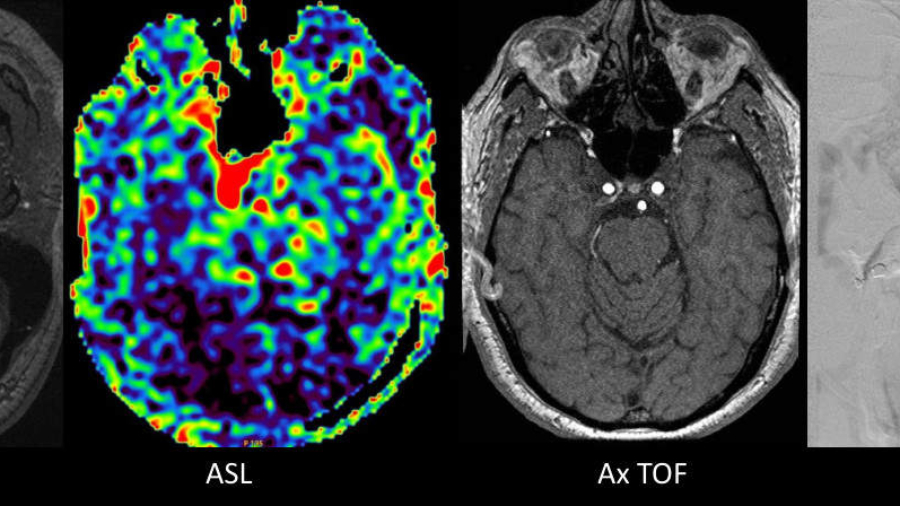

A 71 year old male presented with 1-year history of ocular symptoms (diplopia, proptosis, episcleral congestion).

A 30 year old female with headache. What is the diagnosis?

An elderly male, known diabetic with one episode of seizure. What is the diagnosis?